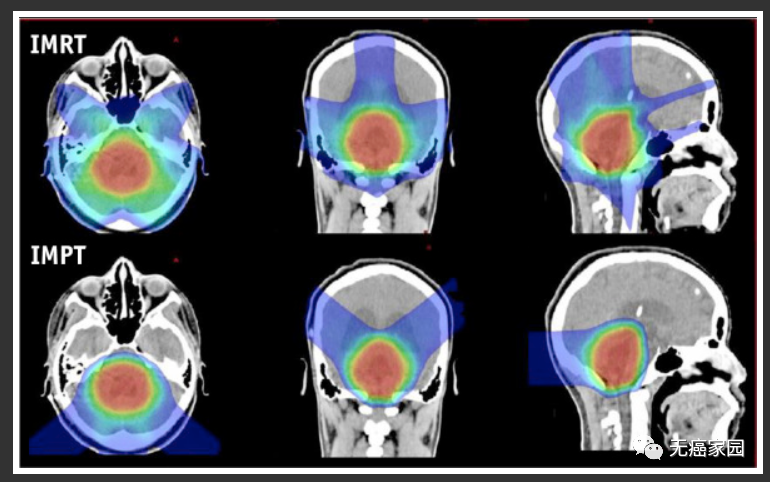

对于后颅窝室管膜瘤,最有临床意义的差异是质子计划对耳蜗、颞叶和下丘脑-垂体轴的剂量较低。

后颅窝室管膜瘤光子(IMRT,顶部)和质子(IMPT,底部)3 个平面的比较图